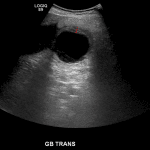

- Multiple gallstones layering in the gallbladder

- Gallbladder is distended with a thickened, hypoechoic wall

- Linear echogenic structures within the gallbladder lumen

Acute cholecystitis

Cholelithiasis with gallbladder distension, gallbladder wall thickening and edema, pericholecystic fluid, and positive sonographic Murphy sign, consistent with acute cholecystitis.

Linear echogenic structures within the gallbladder lumen may represent sloughed membranes, which if true would raise concern for gangrenous cholecystitis.